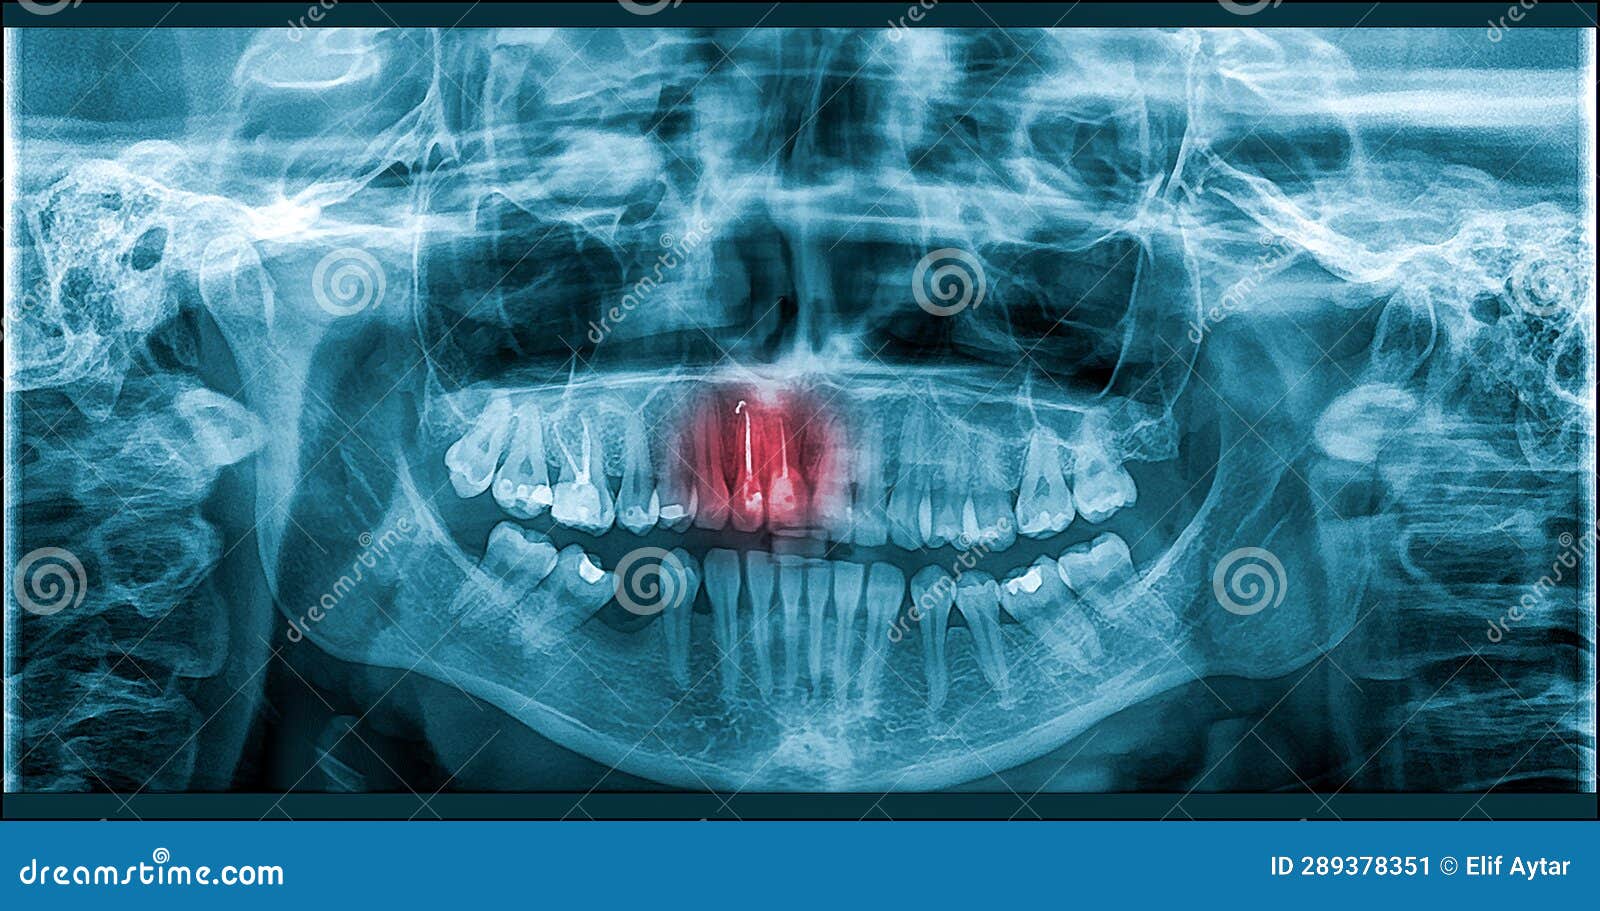

Panoramic xray image of teeth and mouth with wisdom teeth Parkview Tooth Pain After X Ray Most dental pain is caused by an organic problem such as dental caries, periodontitis, pulpitis, or trauma. Due to their close proximity, your body may be confused and perceive it as a toothache while it is actually something else. But there are lots of possible reasons why this is happening, from referred pain to hidden problems deep inside your tooth.. Tooth Pain After X Ray.

From www.dreamstime.com